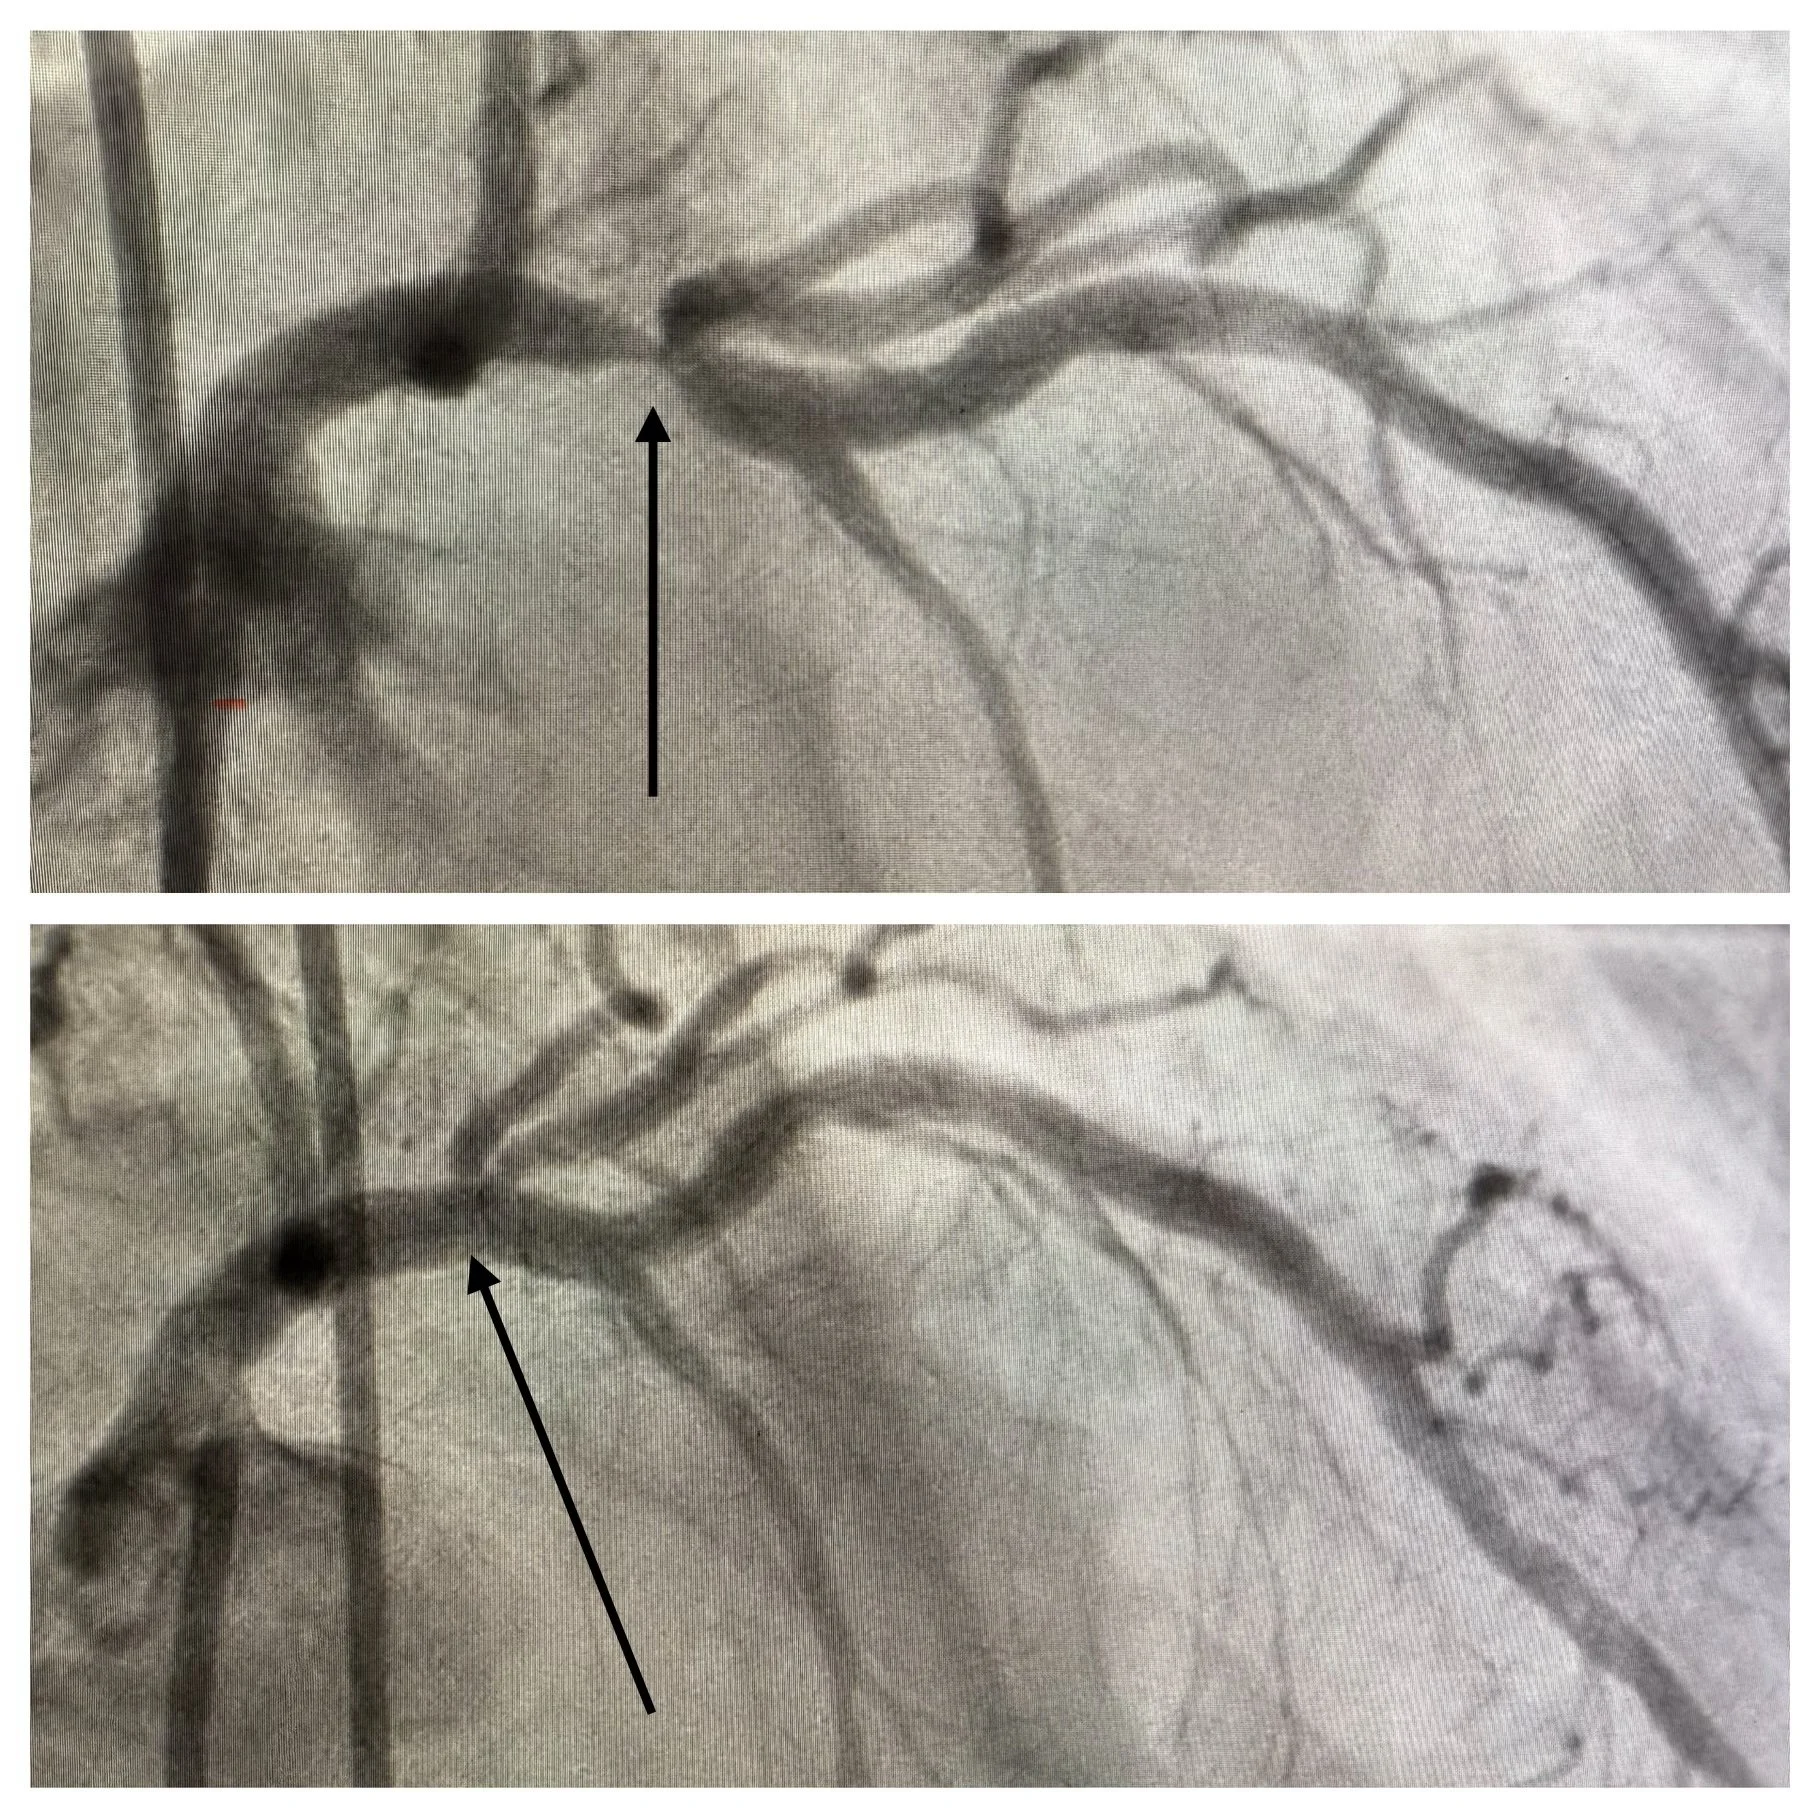

I just got home from a followup visit with my cardiologist. I still have some pain, but I'm recovering. He told me how glad he was they were able to open the artery with a stent, that based on my condition before the procedure he’d been worried I would have to have bypass surgery. He shared with me the x-ray images from the procedure I had two weeks ago: images before and after the stent was placed (arrow is pointing to where the artery was clogged).